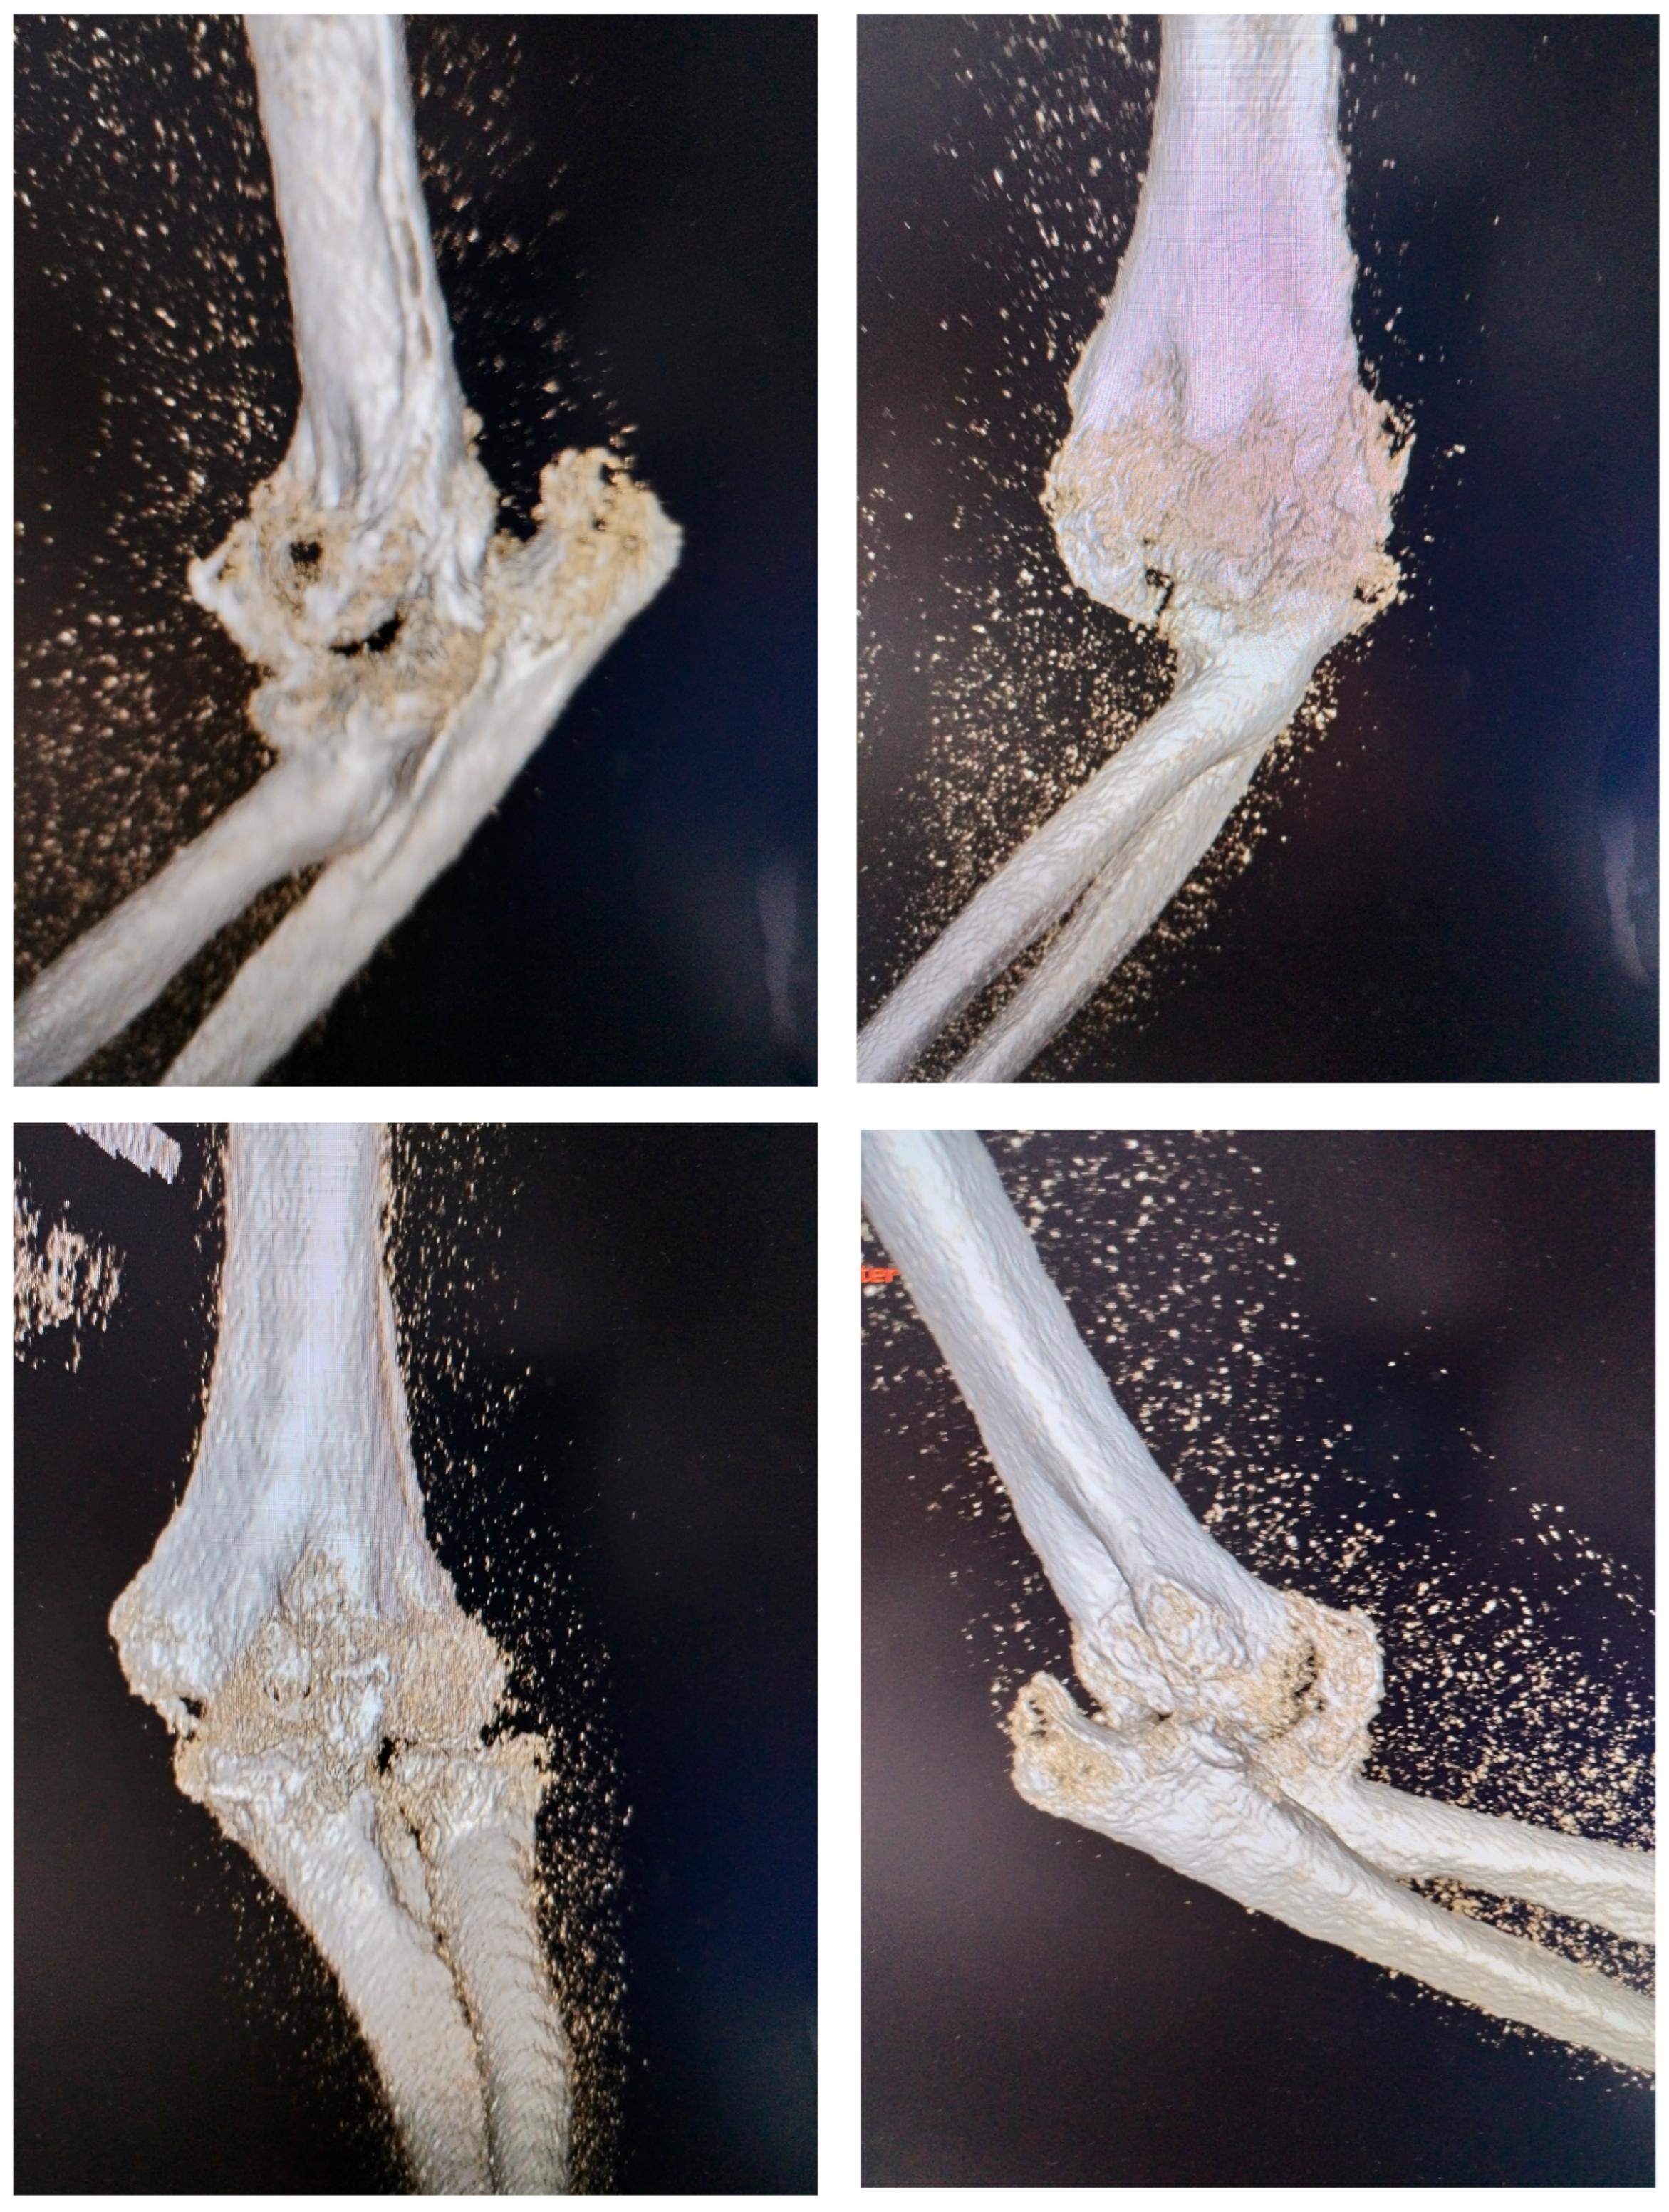

At the time of the injury, the posterior elbow dislocation with associated fractures was not fully diagnosed. The patient initially underwent closed reduction and cast immobilization, but the original radiographs taken immediately after the trauma and following the first reduction were unavailable. Radiographs obtained at the time of admission to our clinic were inconclusive due to extensive heterotopic ossification, prompting a 3D computed tomography (CT) scan to better visualize the bony anatomy and the joint relationships (Figure 2). The CT scan revealed a chronic posterior elbow dislocation with a large heterotopic bone mass within the joint. The coronoid process of the ulna was no longer discernible, suggesting resorption or fragmentation at the time of injury. The radial head was severely deformed (Masson 3), preventing normal articulation with the capitulum and functionally blocking the proximal radioulnar joint.

Figure 2.

3D CT aspect with visualisation of dislocation and presence of a massive heterotopic bone inside the joint.